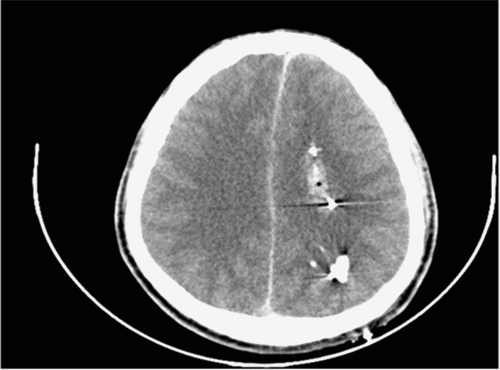

Focused assessment with sonography in trauma (FAST) revealed a diffusely hypokinetic left ventricle without tamponade or pericardial effusion. Initial chest X ray (CXR) demonstrated mild bilateral pulmonary edema (Figure 1A). CT scan of the head showed a ballistic fragment entering the left posterior parietal area, terminating in the left parasagittal anterior frontal lobe without contralateral injury (Figure 2). Imaging also revealed subarachnoid and subdural hematomas with a 3 mm midline shift.

Figure 2. Head CT (superior to inferior views). Published with Permission

Bullet trajectory through the left posterior parietal area, terminating in the left parasagittal anterior frontal lobe. No contralateral injury